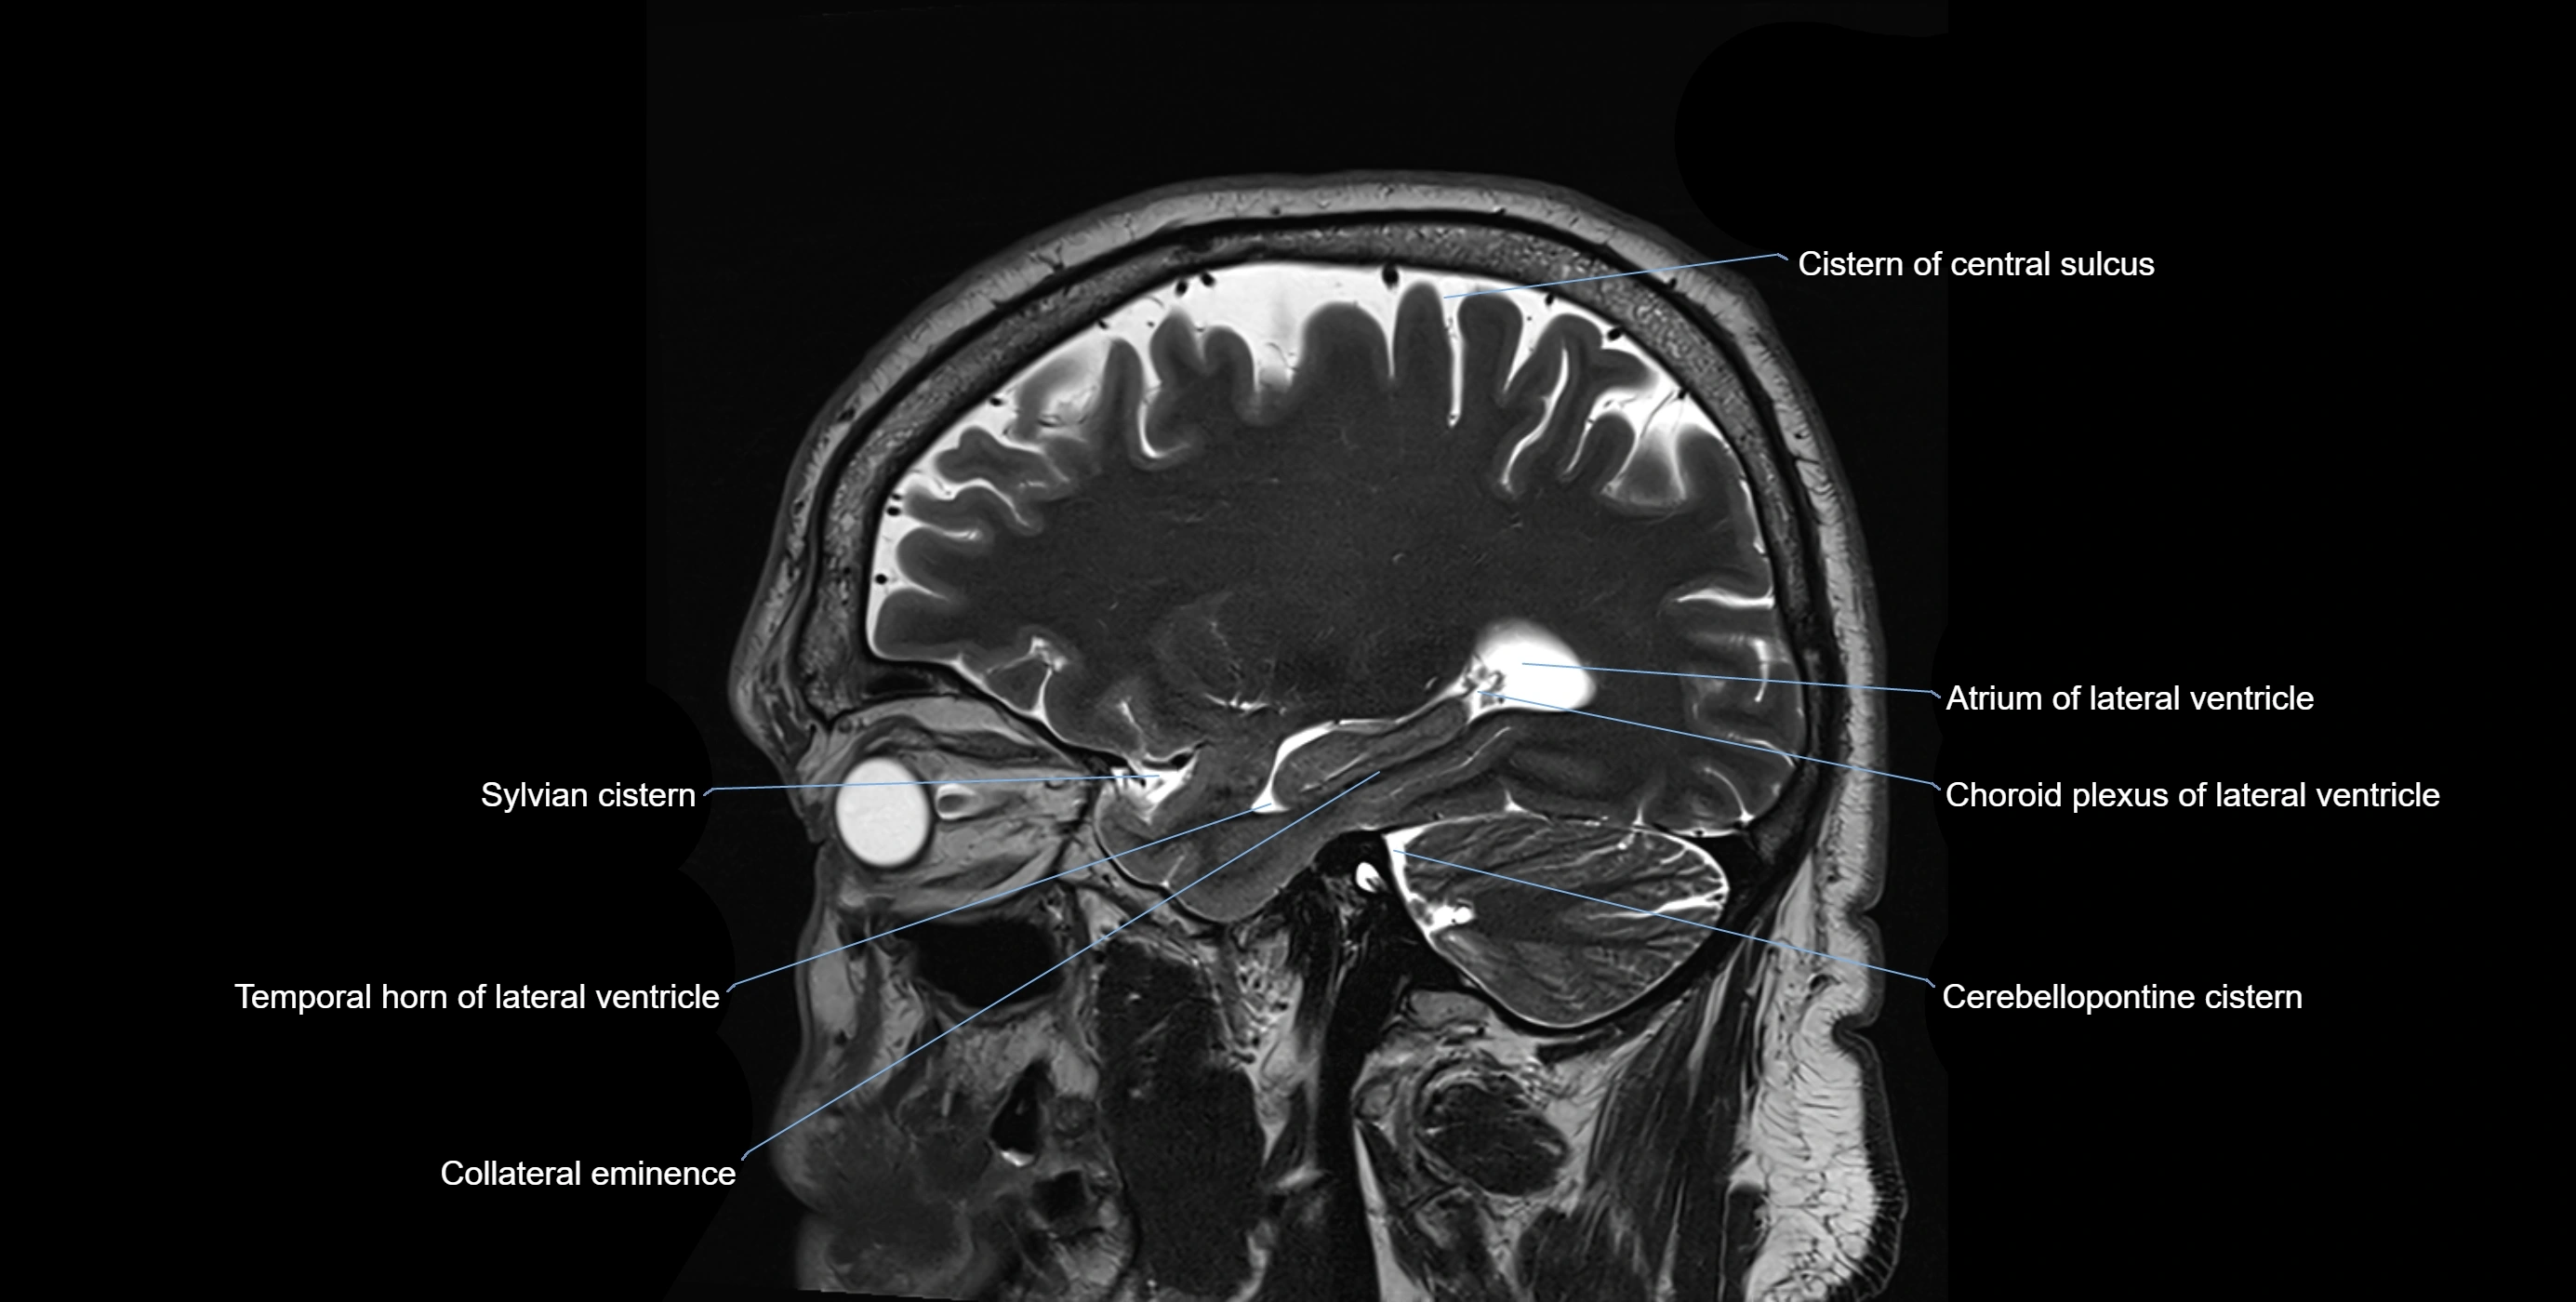

MRI images

image